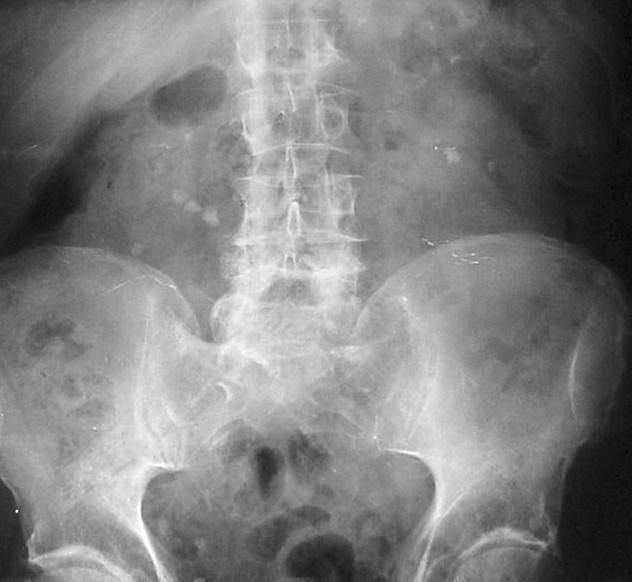

Jak zdiagnozować kamicę nerkową?

Kamicę nerkową diagnozuje się za pomocą jej symptomów przy wykluczeniu innych źródeł choroby. Dla potwierdzenia diagnozy wykonuje się tomografię komputerową, w przypadku kobiet wykonuje się USG w ciąży.